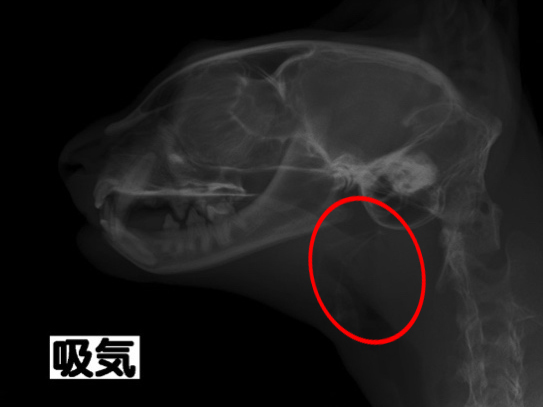

レントゲン検査:赤丸が狭窄部位